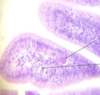

Giemsa staining

Luna shape of sporozoites and merozoites

AVIAN COCCIDIA

Giemsa staining

Luna shape of sporozoites and merozoites